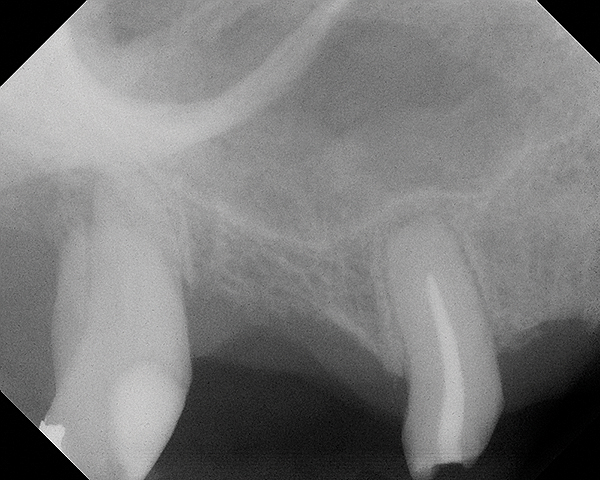

Fig 20. Case 3. Preoperative radiograph showing about 3.5 mm of ridge height.

Figure 20